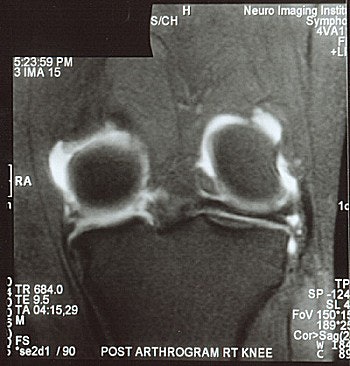

![]() |

| MR arthrogram demonstrates a meniscal re-tear in a patient with >25% meniscal resection. |